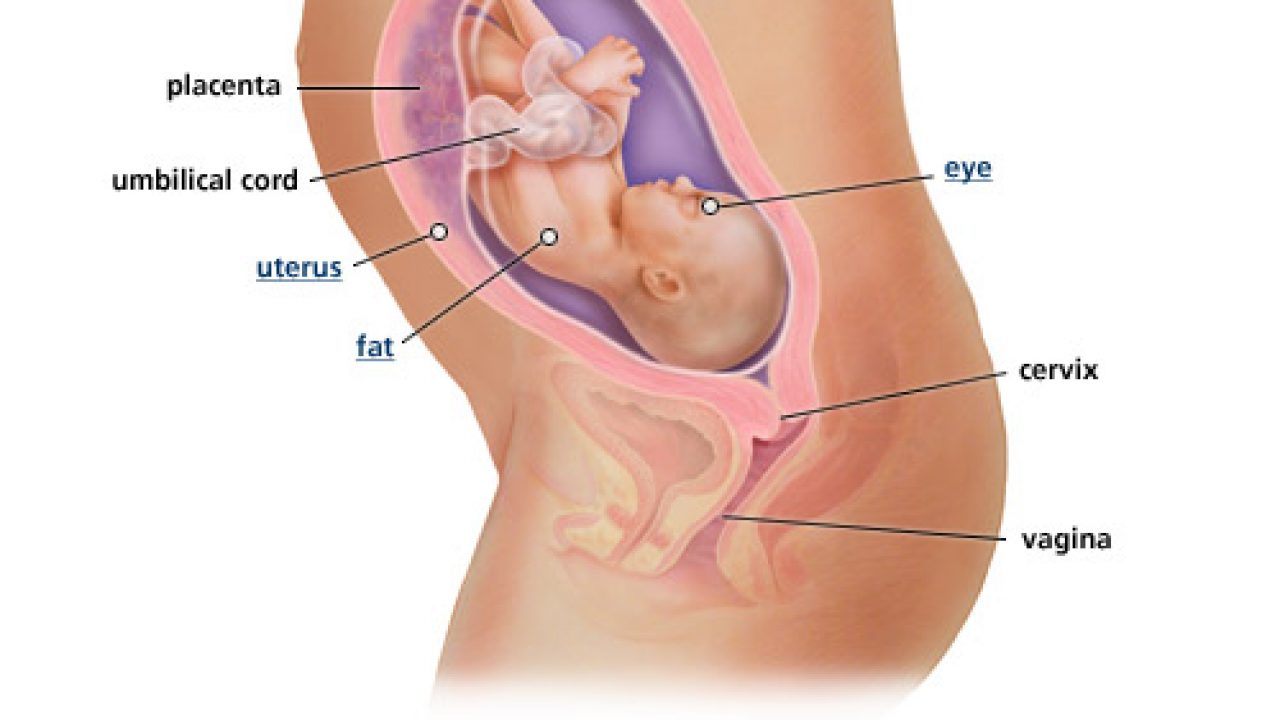

Ini Posisi Bayi 7 Bulan Dalam Kandungan Moms Wajib Tahu Orami

Ini Posisi Bayi 7 Bulan Dalam Kandungan Moms Wajib Tahu Orami

Prenagen World Memasuki Usia Kandungan 7 Bulan Kehamilan Sudah Memasuki Trimester Akhir Di Saat Ini Kamu Bisa Merasakan Perpindahan Posisi Janin Dan Ia Pun Sudah Dapat Menyimpan Lemak Dalam Tubuhnya Selain

Prenagen World Memasuki Usia Kandungan 7 Bulan Kehamilan Sudah Memasuki Trimester Akhir Di Saat Ini Kamu Bisa Merasakan Perpindahan Posisi Janin Dan Ia Pun Sudah Dapat Menyimpan Lemak Dalam Tubuhnya Selain

Perkembangan Janin 7 Bulan 28 Minggu Hamil Co Id

Perkembangan Janin 7 Bulan 28 Minggu Hamil Co Id

Hamil 7 Bulan Bayi Mulai Berada Di Posisi Siap Lahir Alodokter

Hamil 7 Bulan Bayi Mulai Berada Di Posisi Siap Lahir Alodokter

Informasi Perkembangan Janin 28 Minggu Dan Perubahan Tubuh Ibu Alodokter

Informasi Perkembangan Janin 28 Minggu Dan Perubahan Tubuh Ibu Alodokter